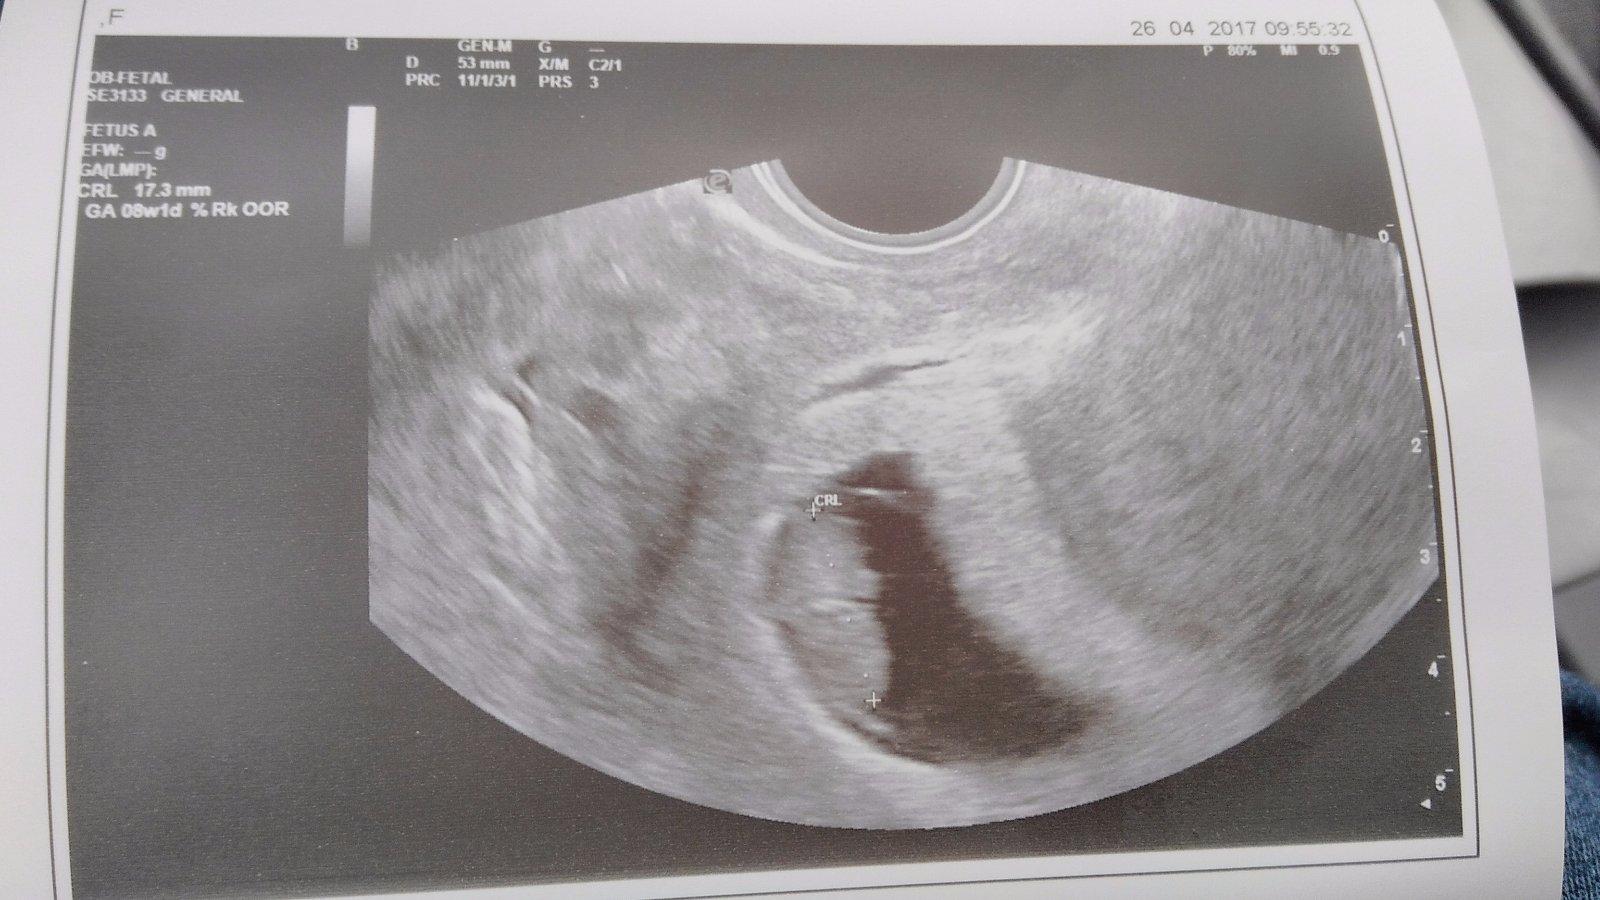

Konečne mam výsledky z krvi od dr na hcg hormon. Som tehotna 🙂 HCG 475 jednotiek, ze to vyzera na 4tt...nie je to malo??? Ms som mala 13 mar a ovu bola 7-8 aprila

no ak dobre ratam ( to len tak zaokruhlujem ), tak si mala cyklus dlhysi a teda mala 3t do ovulky a potom presli zhruba 2t, cize sice to dokopy je 5tt, ale babo je velke presne ako v tom cykle, ktory som popisala na zaciatku, cize velkostne je na 4tt. a teda aj HCG nestupa kazdej rovnako. tam su tiez pomerne velke referencne hodnoty.

@ejuska2586 jj mam uz aj potvrdene tehu od dr 😉 v utorok idem znovu na krv a na utz 🙂